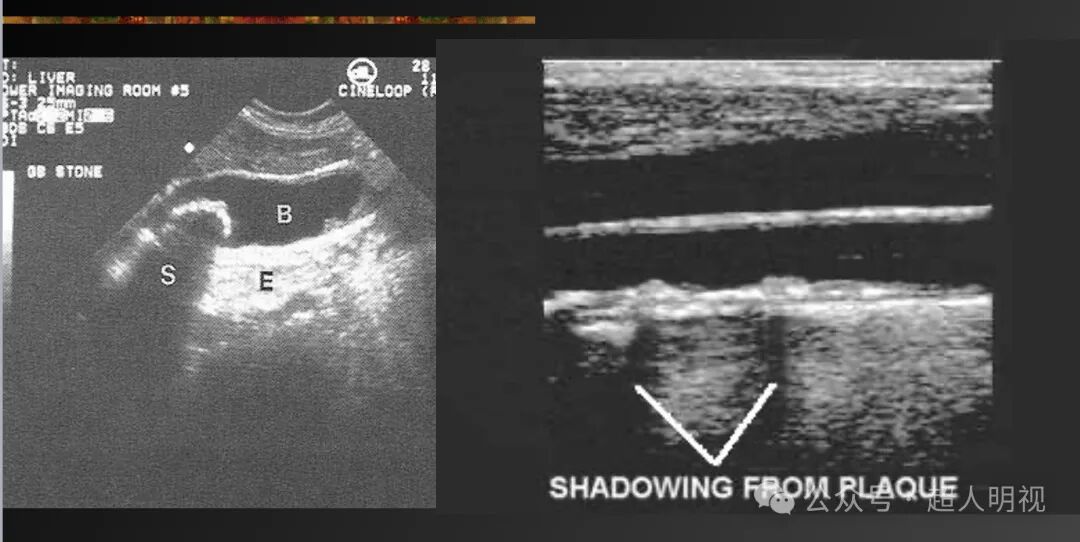

- 声影(强衰减结构后方回声减弱)

彩超伪像是什么超声伪像_https://www.jmylbn.com_新闻资讯_第3张

- 边缘声影(弯曲界面处的声束偏折和折射导致衰减)

彩超伪像是什么超声伪像_https://www.jmylbn.com_新闻资讯_第4张